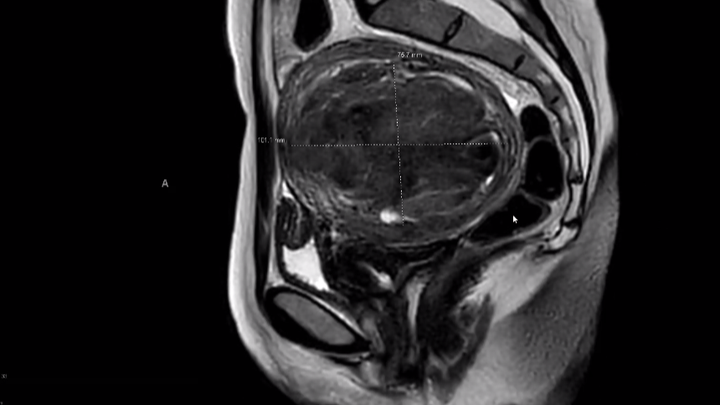

It’s difficult to sit down and write this- with fear of publicly sharing such an intimate health issue, and shame in asking for help when there are so many other people needing financial assistance within the current climate. On March 17th I’ll have a 12cm fibroid removed from my uterus. Due to the size of the fibroid (anything beyond 10cm is considered large, the size of a grapefruit) it will be removed via abdominal myomectomy. The goal of the abdominal myomectomy is to preserve the health of my uterus and avoid a full hysterectomy.

The following months have been a rollercoaster of learning about my body through followup ultrasounds, OBGYN appointments, meeting with a laparoscopic surgeon, then being referred to a myomectomy surgeon, having an MRI, blood tests, and iron infusions (to reduce the risk of a blood transfusion during surgery). Because of the size of the fibroid it can not be removed laparoscopically and thus the recovery time will be significantly longer, 4-6 weeks. I’m asking for financial assistance to help cover the burden of already taking off so many days for preliminarily doctors appointments/surgical planning, as well as the month+ I’ll have to take off to heal from the surgery. Truly anything helps. If you’ve read this far I love you, thank you for caring. If you’re unable to donate but still want to help I would appreciate any meal dropoffs, book loans, handwritten poems, movie recommendations or just hello’s. Thank you again for reading xx